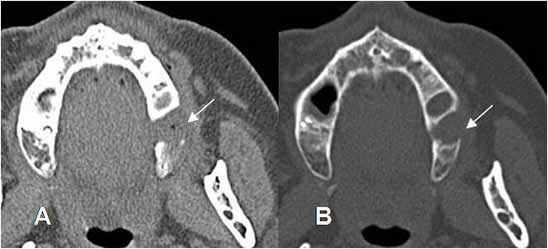

Fig 48. Absceso periapical.

A: TAC reconstrucción y B: TAC reconstrucción coronal. Enfermedad periapical, con destrucción ósea (Flechas delgadas) y prominencia de los tejidos blandos, hacia la superficie lingual (Flechas gruesas), por la formación de absceso periapical.